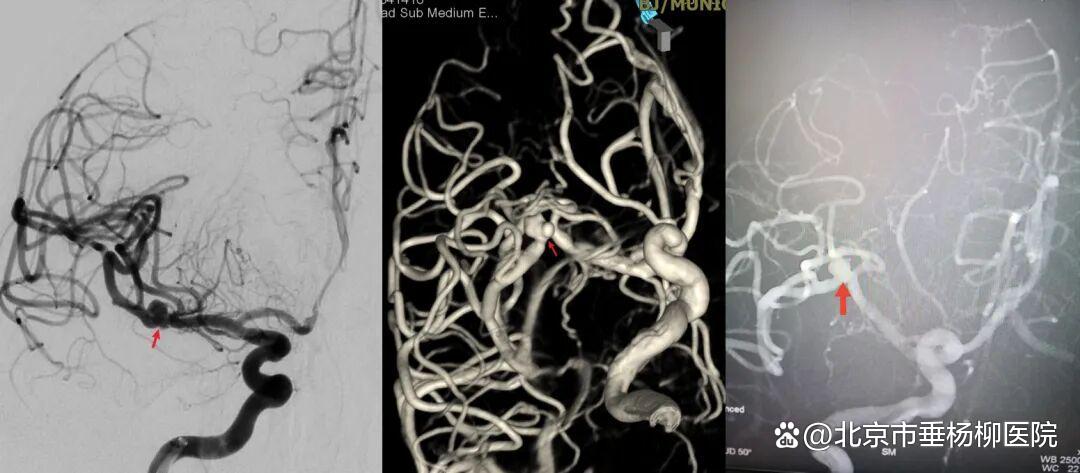

病例一为77岁女性患者,既往高血压病史。因“突发剧烈头痛伴恶心2天”前来清华大学附属垂杨柳医院急诊科就诊。头颅CT检查提示蛛网膜下腔出血,头颈动脉CTA提示右侧大脑中动脉M1段分叉处宽颈动脉瘤。神经外科脑血管病介入团队急诊为患者实施了全脑血管造影术(DSA),造影显示动脉瘤不规则,可见子囊,宽颈,主要累及下干。团队采取了支架辅助弹簧圈栓塞术,患者颅内“不定时炸弹”被成功拆除。动脉瘤达到致密栓塞,载瘤动脉通畅。住院半个月后顺利出院,无神经功能障碍。

▲术前DSA显示宽颈动脉瘤,有子囊,主要累及下干

▲术后DSA显示动脉瘤致密栓塞,载瘤动脉通畅